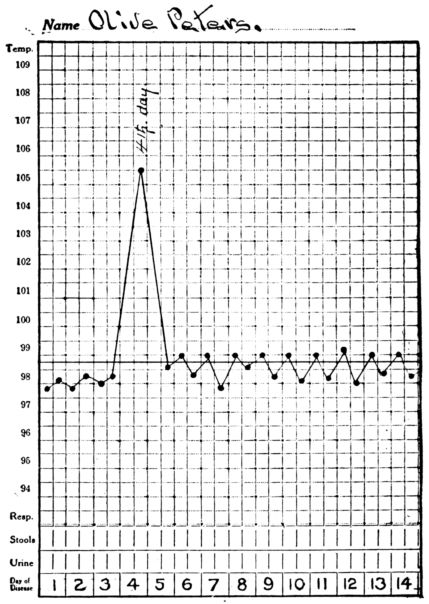

| 8. | Showing rise in temperature in inanition fever | 520 |